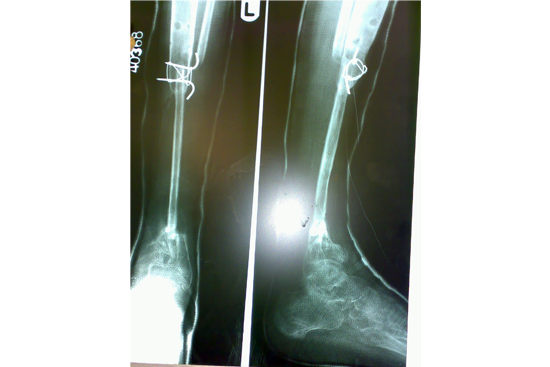

Tibialisation of Fibula

Method

We have done Huntington technique by stage ilizarov procedure. Here is the diagrammatic representation of our method.